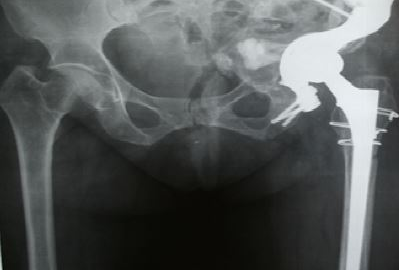

The experience of using custom-made implants for gross acetabular defects